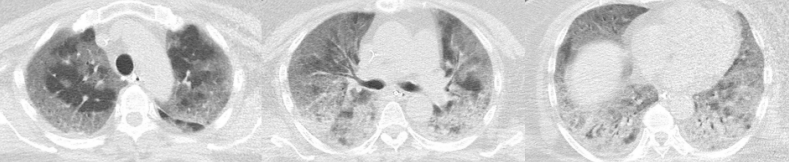

急诊胸部CT:双肺多发斑片影,胸膜下渗出为主。

图片

胸部CT提示双肺对称分布的多发斑片影